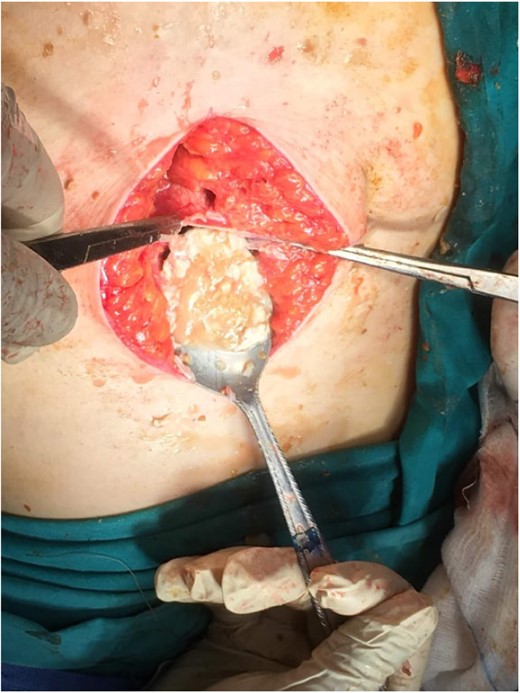

Subsequently, surgical exploration was performed. A preperitoneal sizable cyst was revealed, which developed in the abdominal wall without the involvement of any abdominal viscera or wall peritoneum. The macroscopic appearance of its content suggested that the mass was indeed a hydatid cyst (Figs 4 and 5). Incision upon the cyst wall and evacuation of its content were performed, without spilling of the content. Hypertonic solution of sodium chloride (NaCl 15%) was then injected in the remaining cavity, followed by the placement of a Pezzer catheter.

Intra-operative finding. Cyst content, indicating a hydatid cyst.